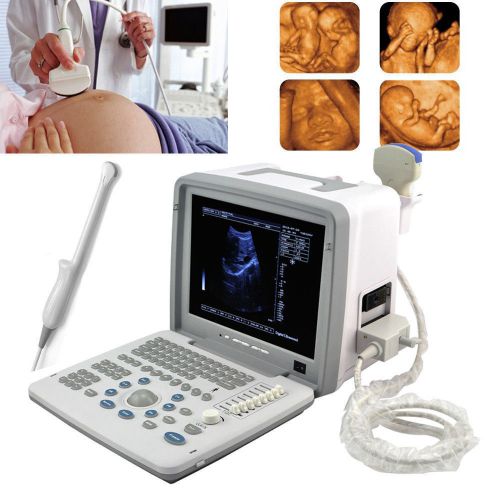

Brand | Denshine |

| Output interface | 2 SVGA video outputs | ||

| Output interface 1 | SVGA color monitor circumscribed | ||

| Screen | 12-inch SVGA high resolution monitor | ||

| Output interface 2 | 2 PAL video outputs | ||

| technology | Full digital imaging technology | ||

| Probes optional | convex linear transvaginal rectal | ||

| software | abundant built-in software packages | ||

| equipment potional | printer trolly | ||

| probe connectors | two | ||

| Approved | CE FDA | ||

| 3D | 3D Ultrasound image working station |